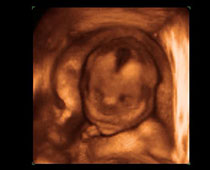

- Fetal Face Ultrasound Photos

- 3D Fetal Profile Ultrasound Scan Photos

- The Clinical Advantages of 3D and 4D Ultrasound

- Definition and Features of Four Dimensional Ultrasound